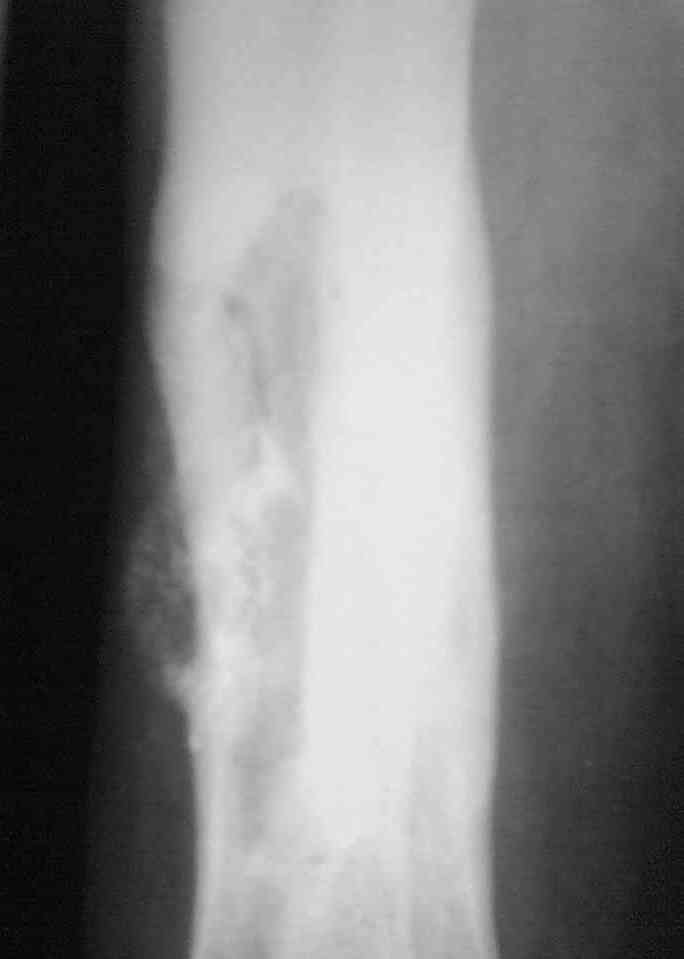

Выкладываю снимки в хронологическом порядке. Снмки все какие есть у больного.

Количество не заменяет качества, поэтому не стоит выкладывать весь хлам, какой удастся найти у пациента. Лучше сделать 1)свежие 2)хорошего качества рентгенограммы, чтобы оценивать ситуацию по ним, а не по мутным огрызкам.